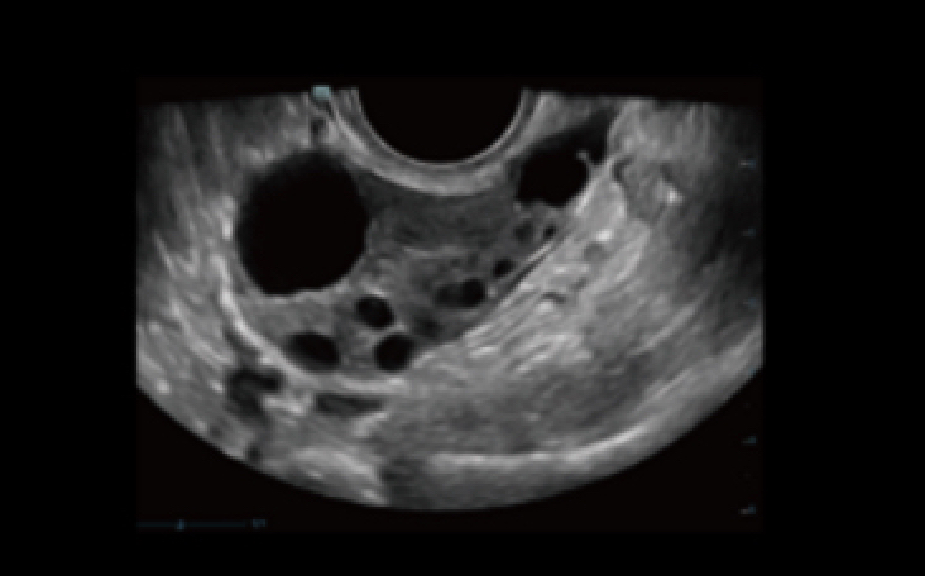

Obstetricia y ginecologĂa

-antes del embarazo

Antes del embarazo

CuantificaciĂłn eficiente para el endometrio

Antes del embarazo